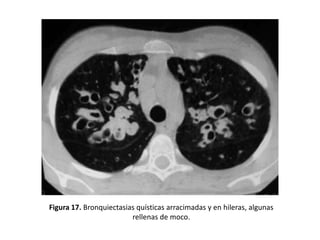

• Impactos mucoides:

– Imágenes tubulares con densidad de partes blandas que representan

el bronquio dilatado y repleto de moco: “bronquio en positivo”, o con

niveles hidroaéreos.

– Pueden aparecer como opacidades lobuladas, en dedo de guante,

ramificadas (en forma de Y o de V) o redondeadas (cuando el plano de

corte es transversal al impacto mucoso se pueden confundir con una

arteria). (Figura 16 y 17).

Figura 17. Bronquiectasias quísticas arracimadas y en hileras, algunas

rellenas de moco.

• Quísticas:

– Es la expresión más grave de la enfermedad.

– Los bronquios adquieren una forma sacular o de

quiste.

– Pueden presentar niveles hidroaéreos o estar

agrupadas en racimos o hileras.

– Adoptan la típica imagen de “nido de golondrina”

cuando el moco se acumula dentro de las lesiones y

aparece un nivel hidroaéreo (Figuras 11, 14, 15, 17, 21

y 25).

– Son frecuentes en la aspergilosis broncopulmonar

alérgica (ABPA) y en la fibrosis quística